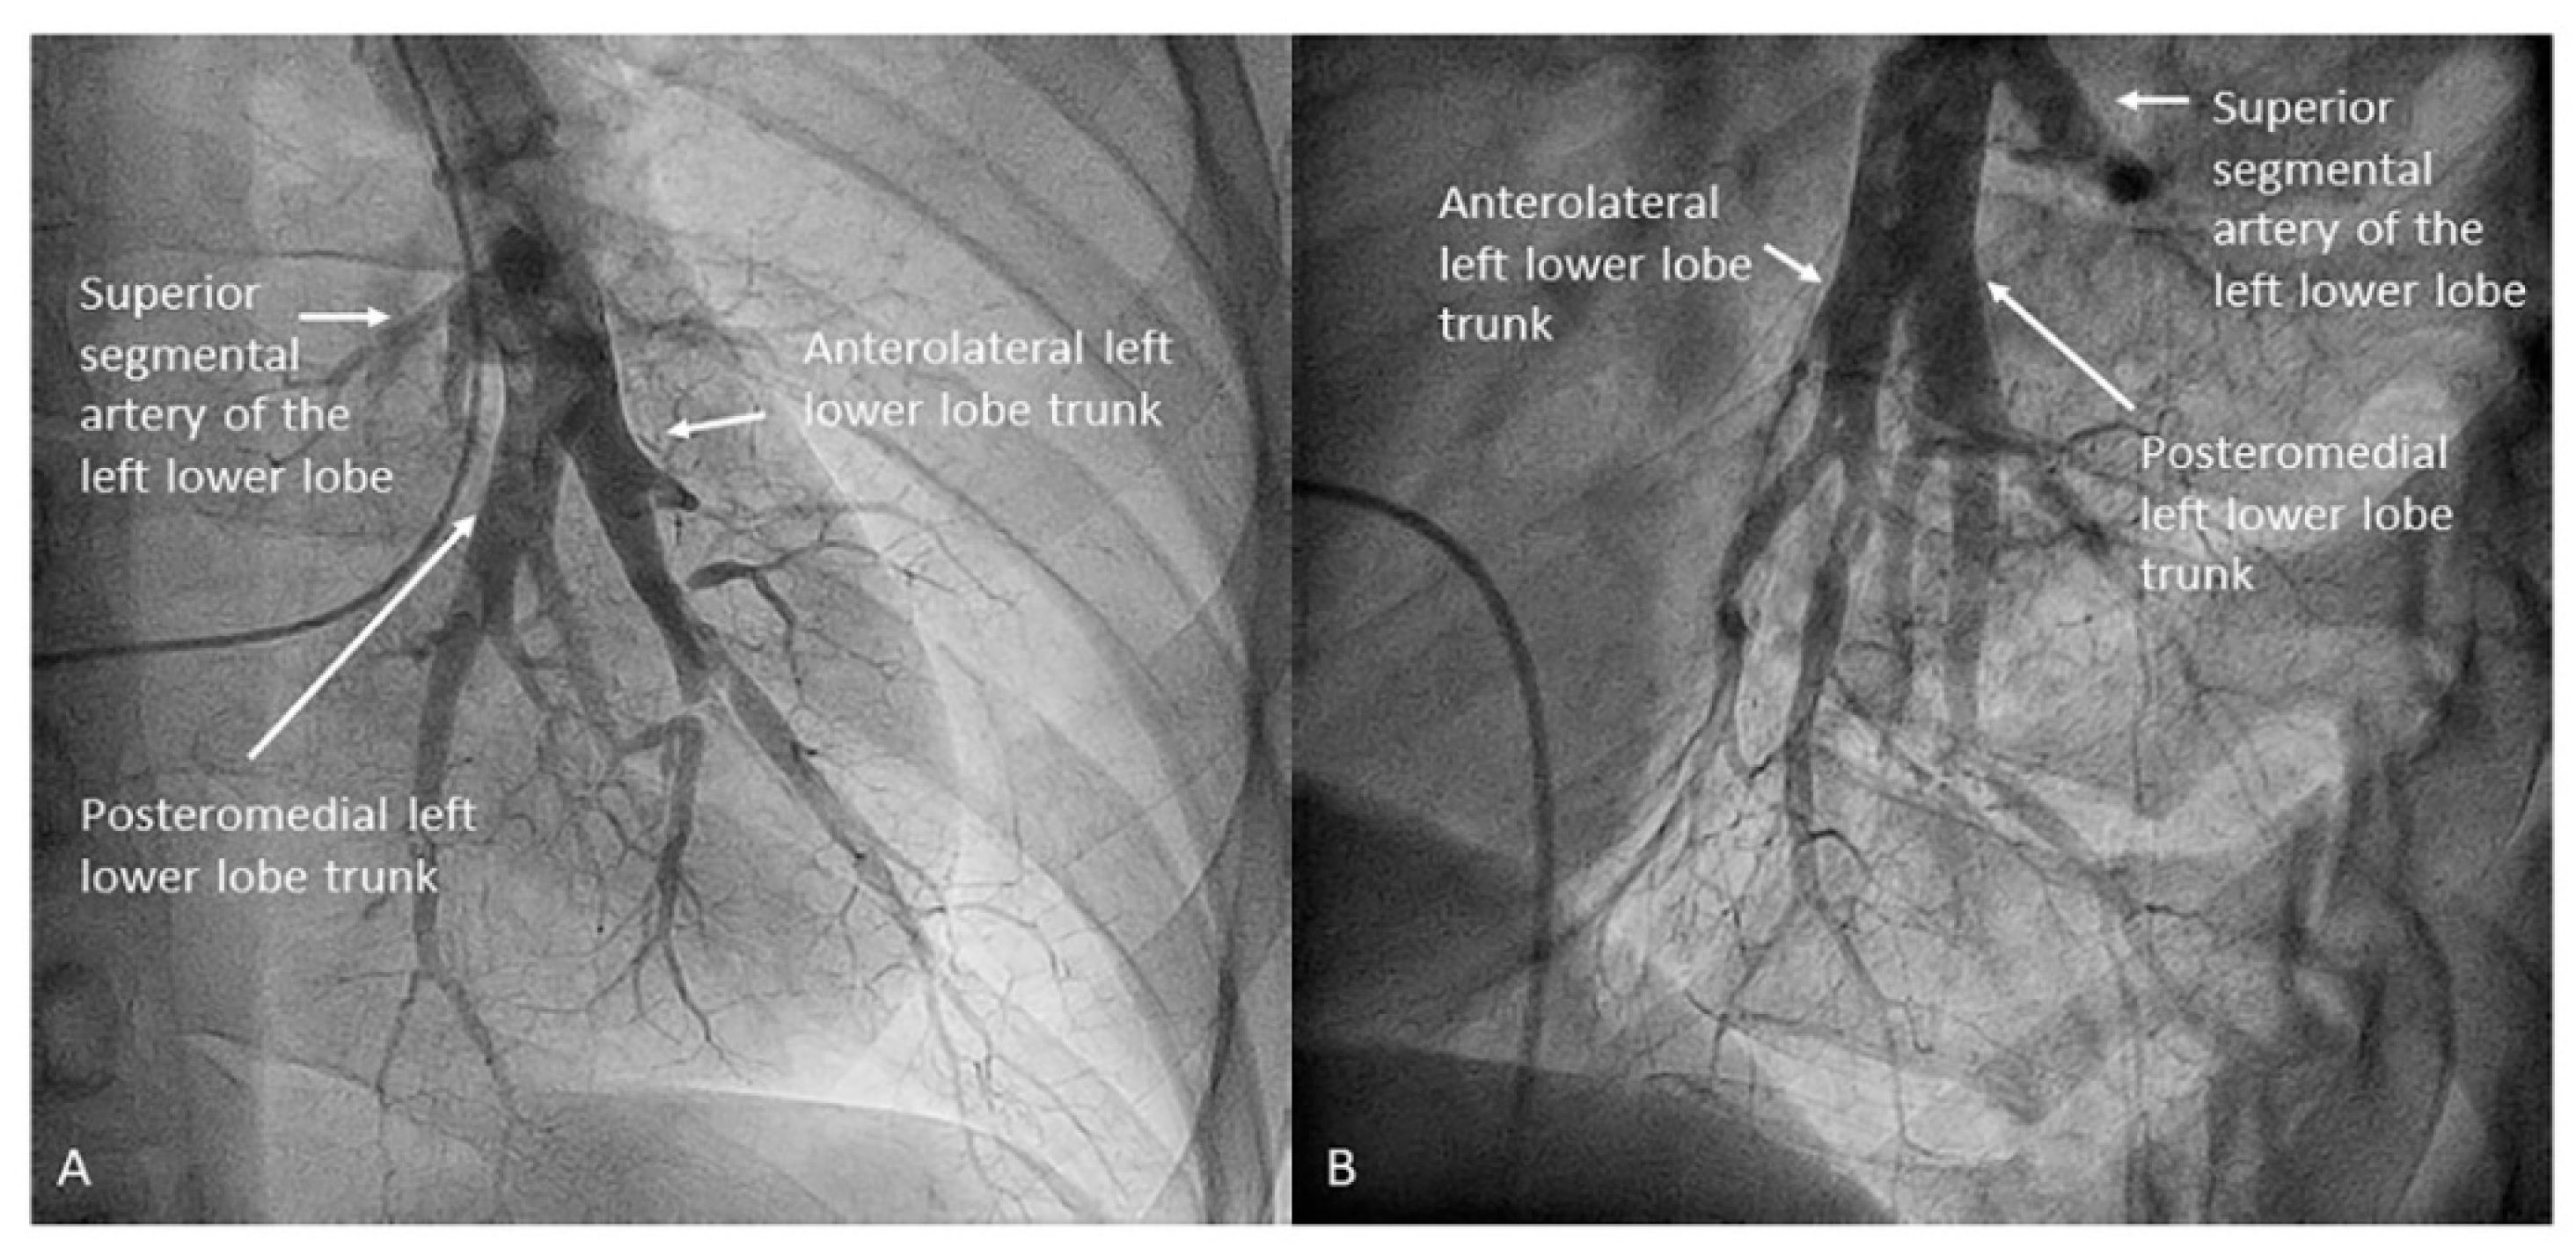

- Left lower lobe. The two trunks of the basal pyramid and the superior segmental artery (A6) are easily cannulated with the MP-A2 in the lateral projection (Figure 26). The anterolateral trunk (A8/9) sometimes requires the Judkins right (JR) 4 or the JL 3.5/4. We should sequentially film both trunks and the superior segmental artery (A6) in the lateral and AP view.